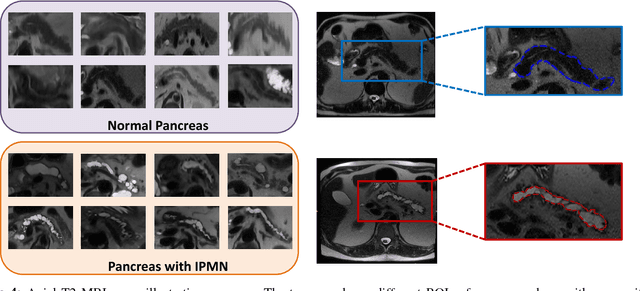

Abstract:Intraductal papillary mucinous neoplasm (IPMN) is a precursor to pancreatic ductal adenocarcinoma. While over half of patients are diagnosed with pancreatic cancer at a distant stage, patients who are diagnosed early enjoy a much higher 5-year survival rate of $34\%$ compared to $3\%$ in the former; hence, early diagnosis is key. Unique challenges in the medical imaging domain such as extremely limited annotated data sets and typically large 3D volumetric data have made it difficult for deep learning to secure a strong foothold. In this work, we construct two novel "inflated" deep network architectures, $\textit{InceptINN}$ and $\textit{DenseINN}$, for the task of diagnosing IPMN from multisequence (T1 and T2) MRI. These networks inflate their 2D layers to 3D and bootstrap weights from their 2D counterparts (Inceptionv3 and DenseNet121 respectively) trained on ImageNet to the new 3D kernels. We also extend the inflation process by further expanding the pre-trained kernels to handle any number of input modalities and different fusion strategies. This is one of the first studies to train an end-to-end deep network on multisequence MRI for IPMN diagnosis, and shows that our proposed novel inflated network architectures are able to handle the extremely limited training data (139 MRI scans), while providing an absolute improvement of $8.76\%$ in accuracy for diagnosing IPMN over the current state-of-the-art. Code is publicly available at https://github.com/lalonderodney/INN-Inflated-Neural-Nets.

Abstract:Pancreatic cancer has the poorest prognosis among all cancer types. Intraductal Papillary Mucinous Neoplasms (IPMNs) are radiographically identifiable precursors to pancreatic cancer; hence, early detection and precise risk assessment of IPMN are vital. In this work, we propose a Convolutional Neural Network (CNN) based computer aided diagnosis (CAD) system to perform IPMN diagnosis and risk assessment by utilizing multi-modal MRI. In our proposed approach, we use minimum and maximum intensity projections to ease the annotation variations among different slices and type of MRIs. Then, we present a CNN to obtain deep feature representation corresponding to each MRI modality (T1-weighted and T2-weighted). At the final step, we employ canonical correlation analysis (CCA) to perform a fusion operation at the feature level, leading to discriminative canonical correlation features. Extracted features are used for classification. Our results indicate significant improvements over other potential approaches to solve this important problem. The proposed approach doesn't require explicit sample balancing in cases of imbalance between positive and negative examples. To the best of our knowledge, our study is the first to automatically diagnose IPMN using multi-modal MRI.